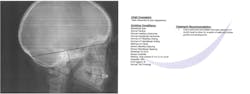

I also recommended that the patient see an oral surgeon for a baseline cone beam computed tomography (CBCT) as well as an orthodontist for a baseline cephalometric analysis (figures 7 and 8). It is important to evaluate the existing skeletal structures and monitor growth over time, so decisions can be made regarding appropriate treatment options and the timing of treatment.

Figure 8